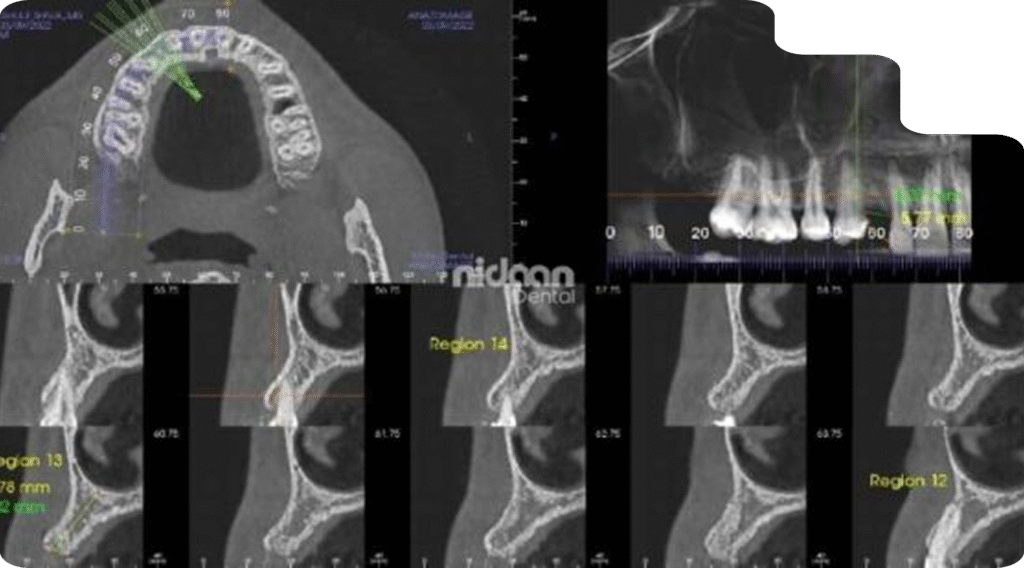

3D Imaging – Cone Beam Computed Tomography (CBCT)

CBCT scans provide a complete 3D view of teeth, bone, and jaw anatomy, crucial for complex dental cases. Dentists rely on CBCT for implant placement, endodontic therapy, orthodontic evaluations, TMJ analysis, and oral surgery. With detailed anatomical visualization, we give clinicians the confidence to achieve predictable and successful outcomes.

3D Imaging - CBCT